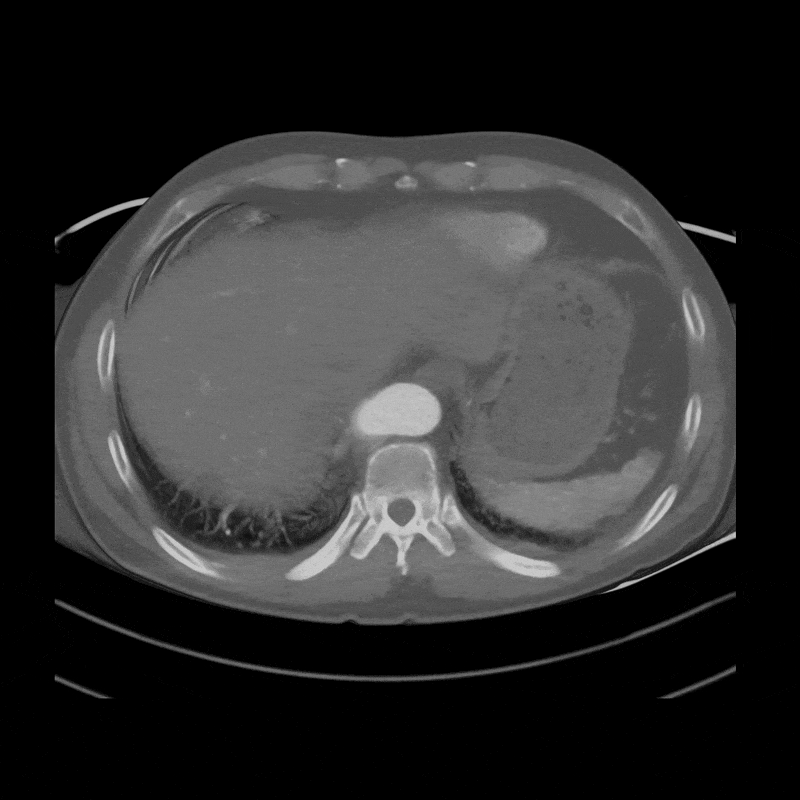

A gated CT angiography of the chest was obtained to generate the images and measurements needed for aortic surveillance. This scan was the most recent in a series of follow-up studies since the patient was first identified with an aortic aneurysm and arch anomalies. The aortic surveillance program relies on these regularly scheduled scans to track changes over time. Measuring data over time is part of a process known as longitudinal analysis, learn more here. In this case, the Kommerell diverticulum has maintained a mostly consistent size over time, while the proximal aortic aneurysm has shown measurable enlargement.

A 3DQ Lab technologist processed the scan using our aortic surveillance protocol. Standardized measurements were taken at set locations along the aorta to ensure consistency with prior studies. Volume-rendered images were generated to visualize the morphology of the aorta and its branch vessels in three dimensions. Curved planar reformats of the coronary arteries were also created to assess their course and relationship to the aortic anatomy. All measurements were then added to the patient’s graph alongside those from previous visits, demonstrating how the size of the aorta has changed over time. Below are the images provided to the Cardiothoracic Surgery team.

Figure F: Standardized aortic diameter measurements obtained at predetermined locations along the thoracic aorta for surveillance.